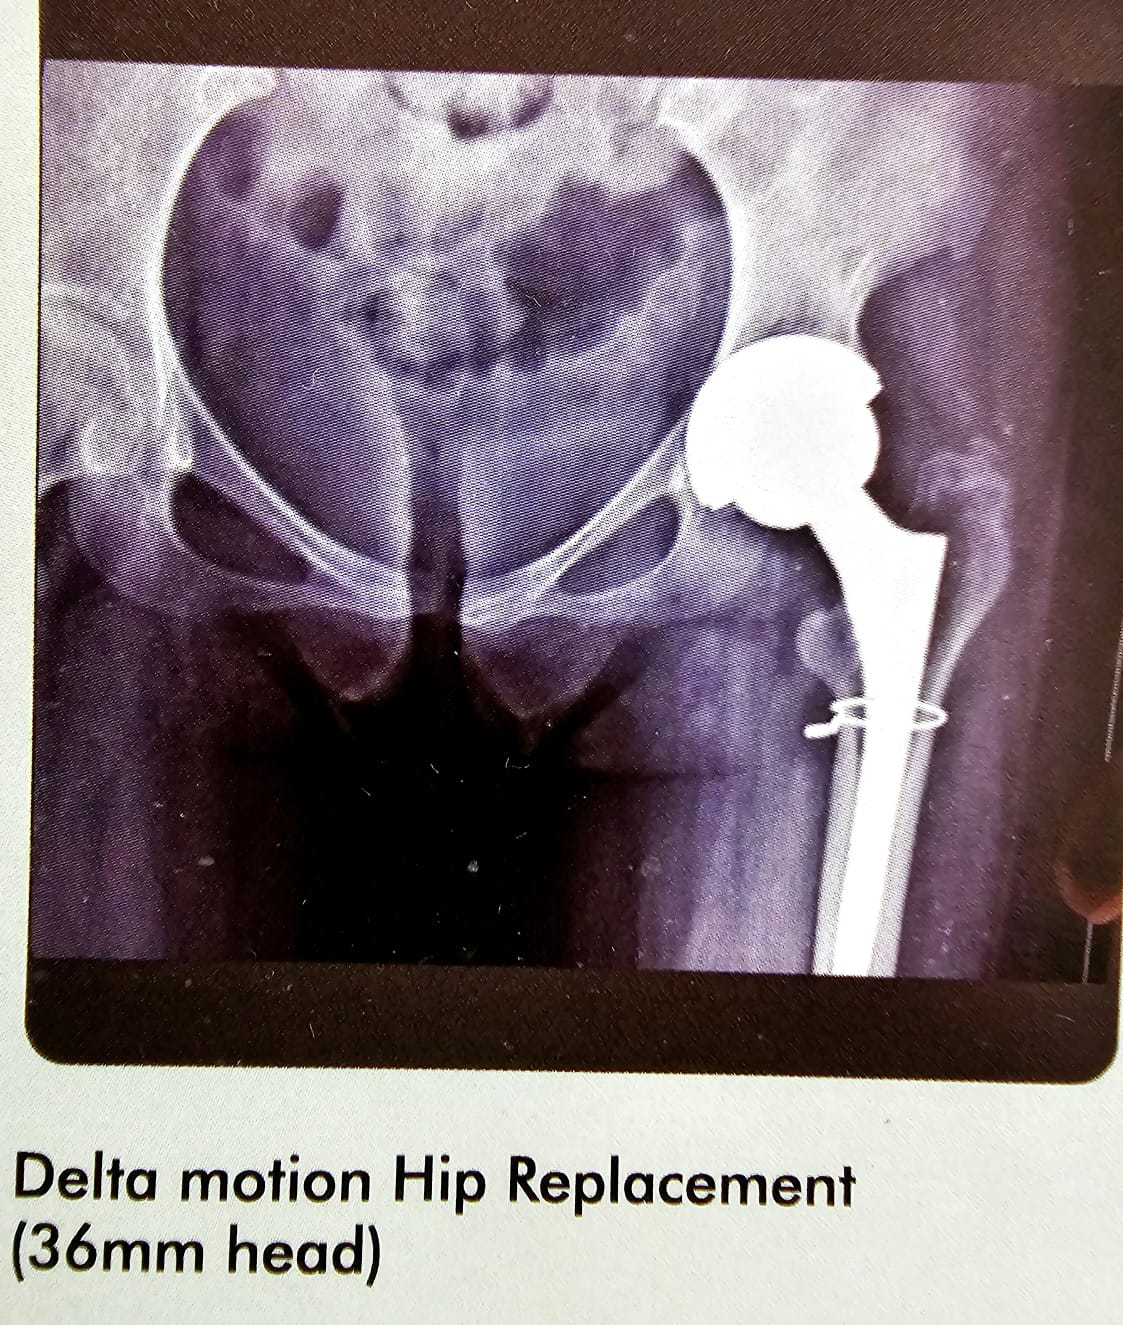

Delta Motion 36mm

This is an interesting case of gentleman from Muscat, and he had a bilateral femural fracture. Fracture of the right neck of femur, which was internally fixed and failed. I did took off the head and neck of the femur on the right side put in THR on the right side with the 36 mm head. And dis reverse intra medullary nail of the femur from the knee joint. Locked it both proximally and distally and on the left side of revision femur nailing was done. Patient did extremely well with no limb and discrepancies